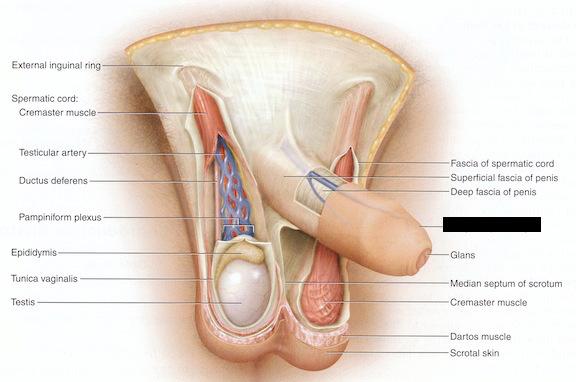

Bulbourethral gland (male)

Corpora cavernosa (pl.) Corpus Cavernosum (s.)

Corpus Spongiosum

Cremaster muscle

Ejaculatory Duct

Epididymis

Glans penis

Prepuce (=foreskin)

Prostate gland

Prostatic/spongy urethra (males)

Scrotum

Seminal vesicle

Seminiferous tubule

Spermatic cord

Testis (s.) Testes (pl.)

Vas deferens (=ductus deferens)